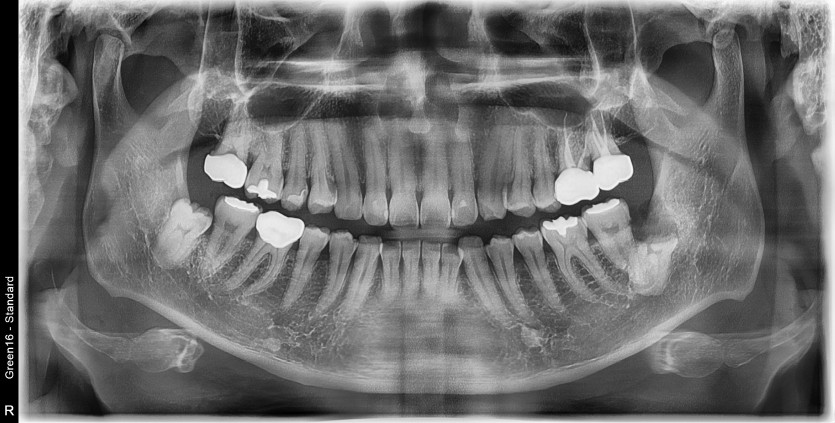

#38 사랑니 발치

구강외과 전문의가 당일발치했습니다.